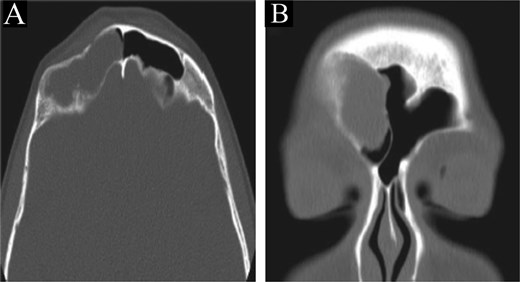

A CT scan of the paranasal sinuses showed a low-attenuation lesion in the right frontal sinus lateral aspect with thinning and resorption of the sinus walls and depression in the posterior side of the anterior wall, suggestive of a depressed fracture (Fig. 4). MRI of the brain and paranasal sinuses showed no thickening of the meninges and no intracranial extension.

CT scan of the brain and paranasal sinuses in (A) axial and (B) coronal views, showing a lesion in the right frontal sinus with resorption of posterior and lateral walls. The anterior wall shows a depressed fracture.